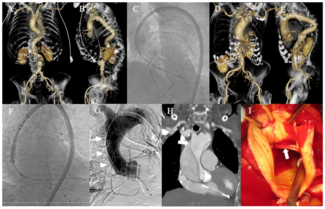

A 69-year-old male with atrial fibrillation radiofrequency ablation 2 years ago was admitted for transcatheter angioplasty of left inferior pulmonary vein (LIPV) stenosis due to recurrent hemoptysis. A cardiac computed tomography (CT) scan...